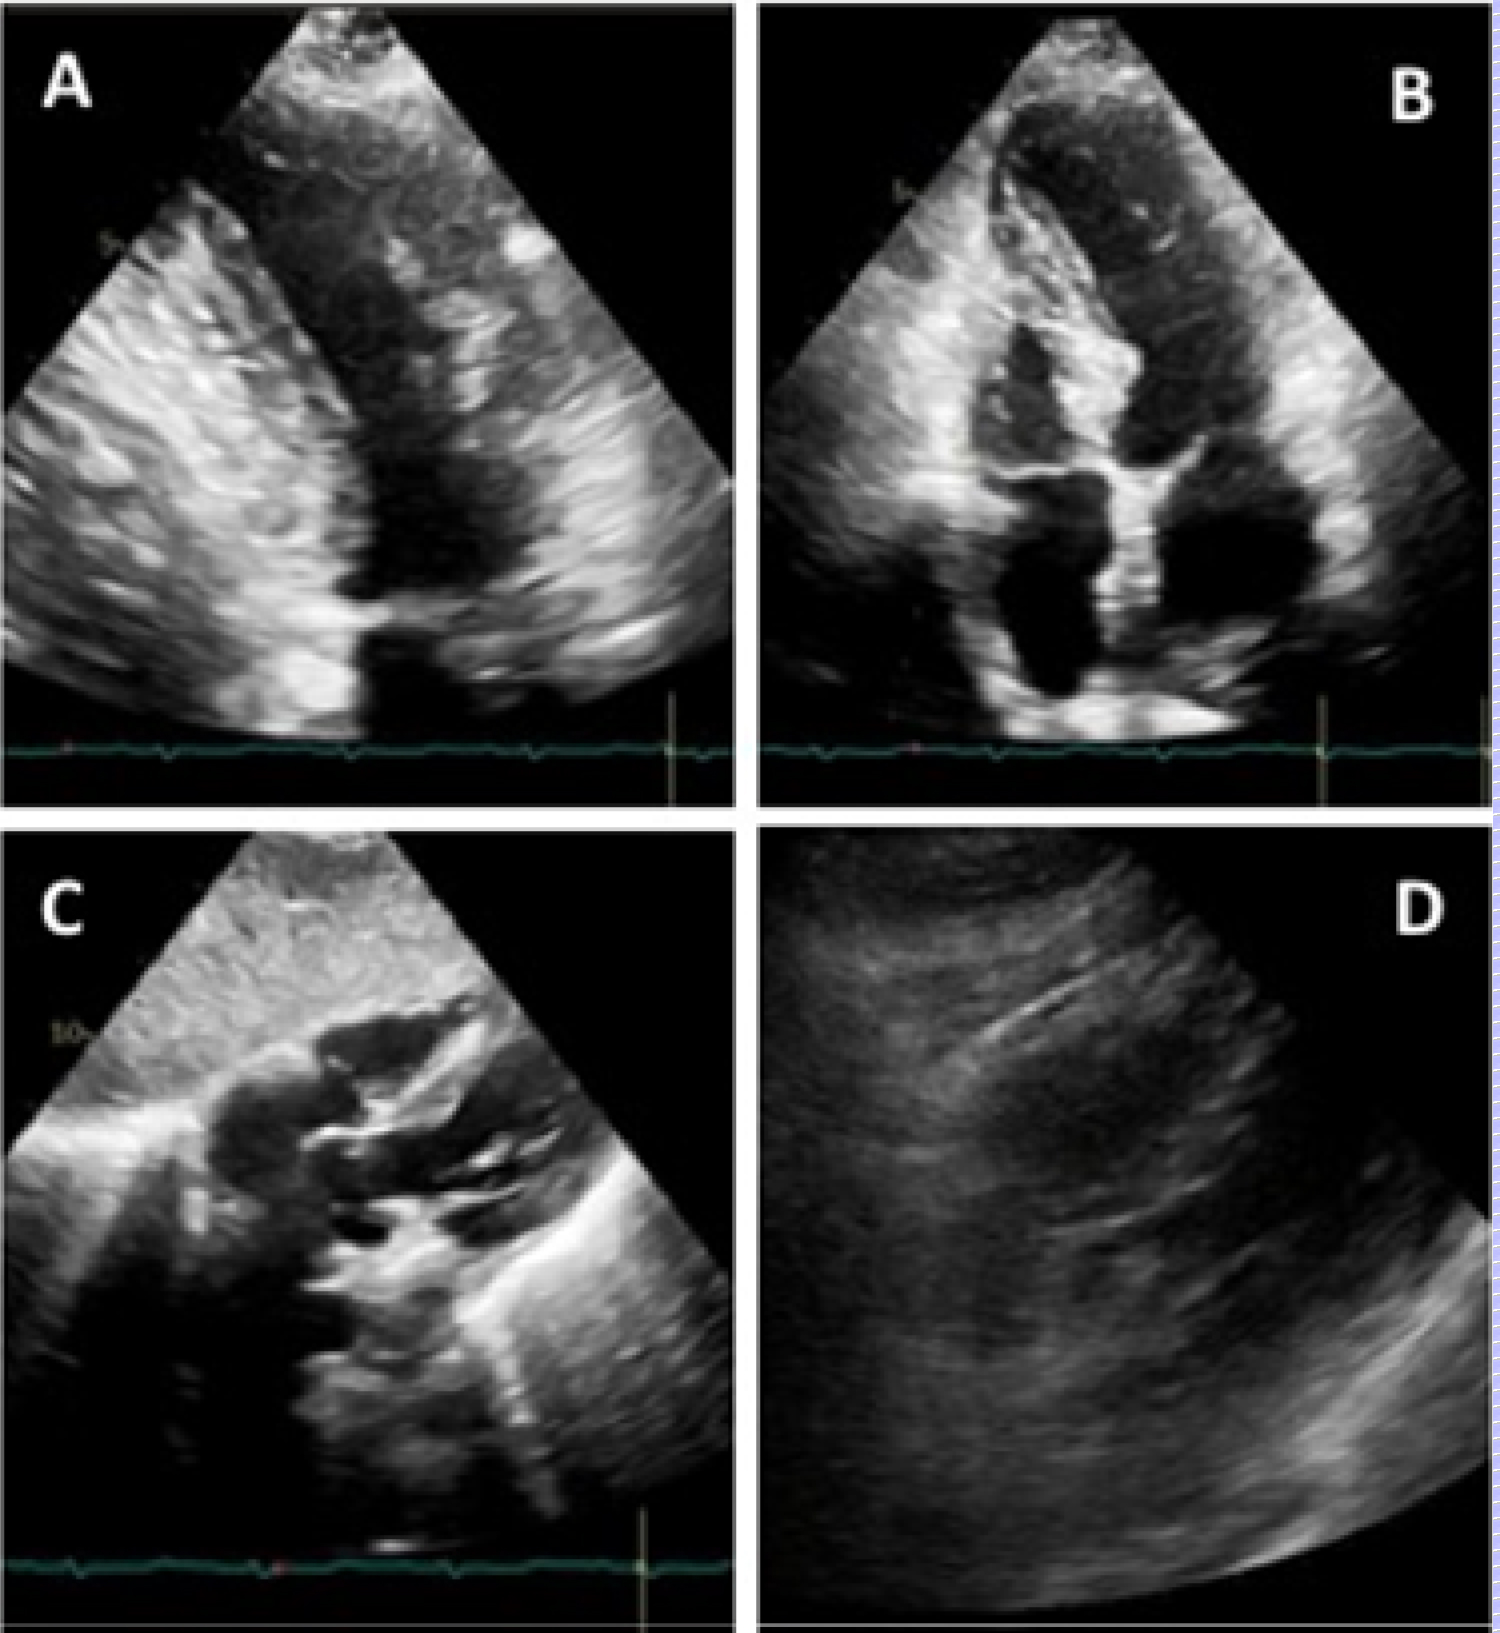

Patient remained hypotensive after procedure with concern for cardiogenic shock. Transthoracic echocardiogram (TTE) confirmed severe hypokinesis in RCA distribution of the inferior wall and right ventricular dysfunction, but also in the LAD territory with hypokinesis of the apical and septal walls with an ejection fraction of 20-25% (Figure 4). He was started on dobutamine infusion but experienced further clinical deterioration. Repeat TTE showed no changes but a small pericardial effusion without hemodynamic significance (Figure 4). A Swan-Ganz catheter was placed with a cardiac index of 1.9 L/min/m2. Patient was deemed to be a poor candidate for further advanced mechanical support. Despite increasing pressor and inotropic support, he passed away on day 7 of hospital admission.

Figure 4: (A) TTE in parasternal long axis view; (B) 4-chamber view; (C) Subcostal view; (D) Short axis view; (E) 2-chamber view; (F) Follow-up TTE with new pericardial effusion. View Figure 4